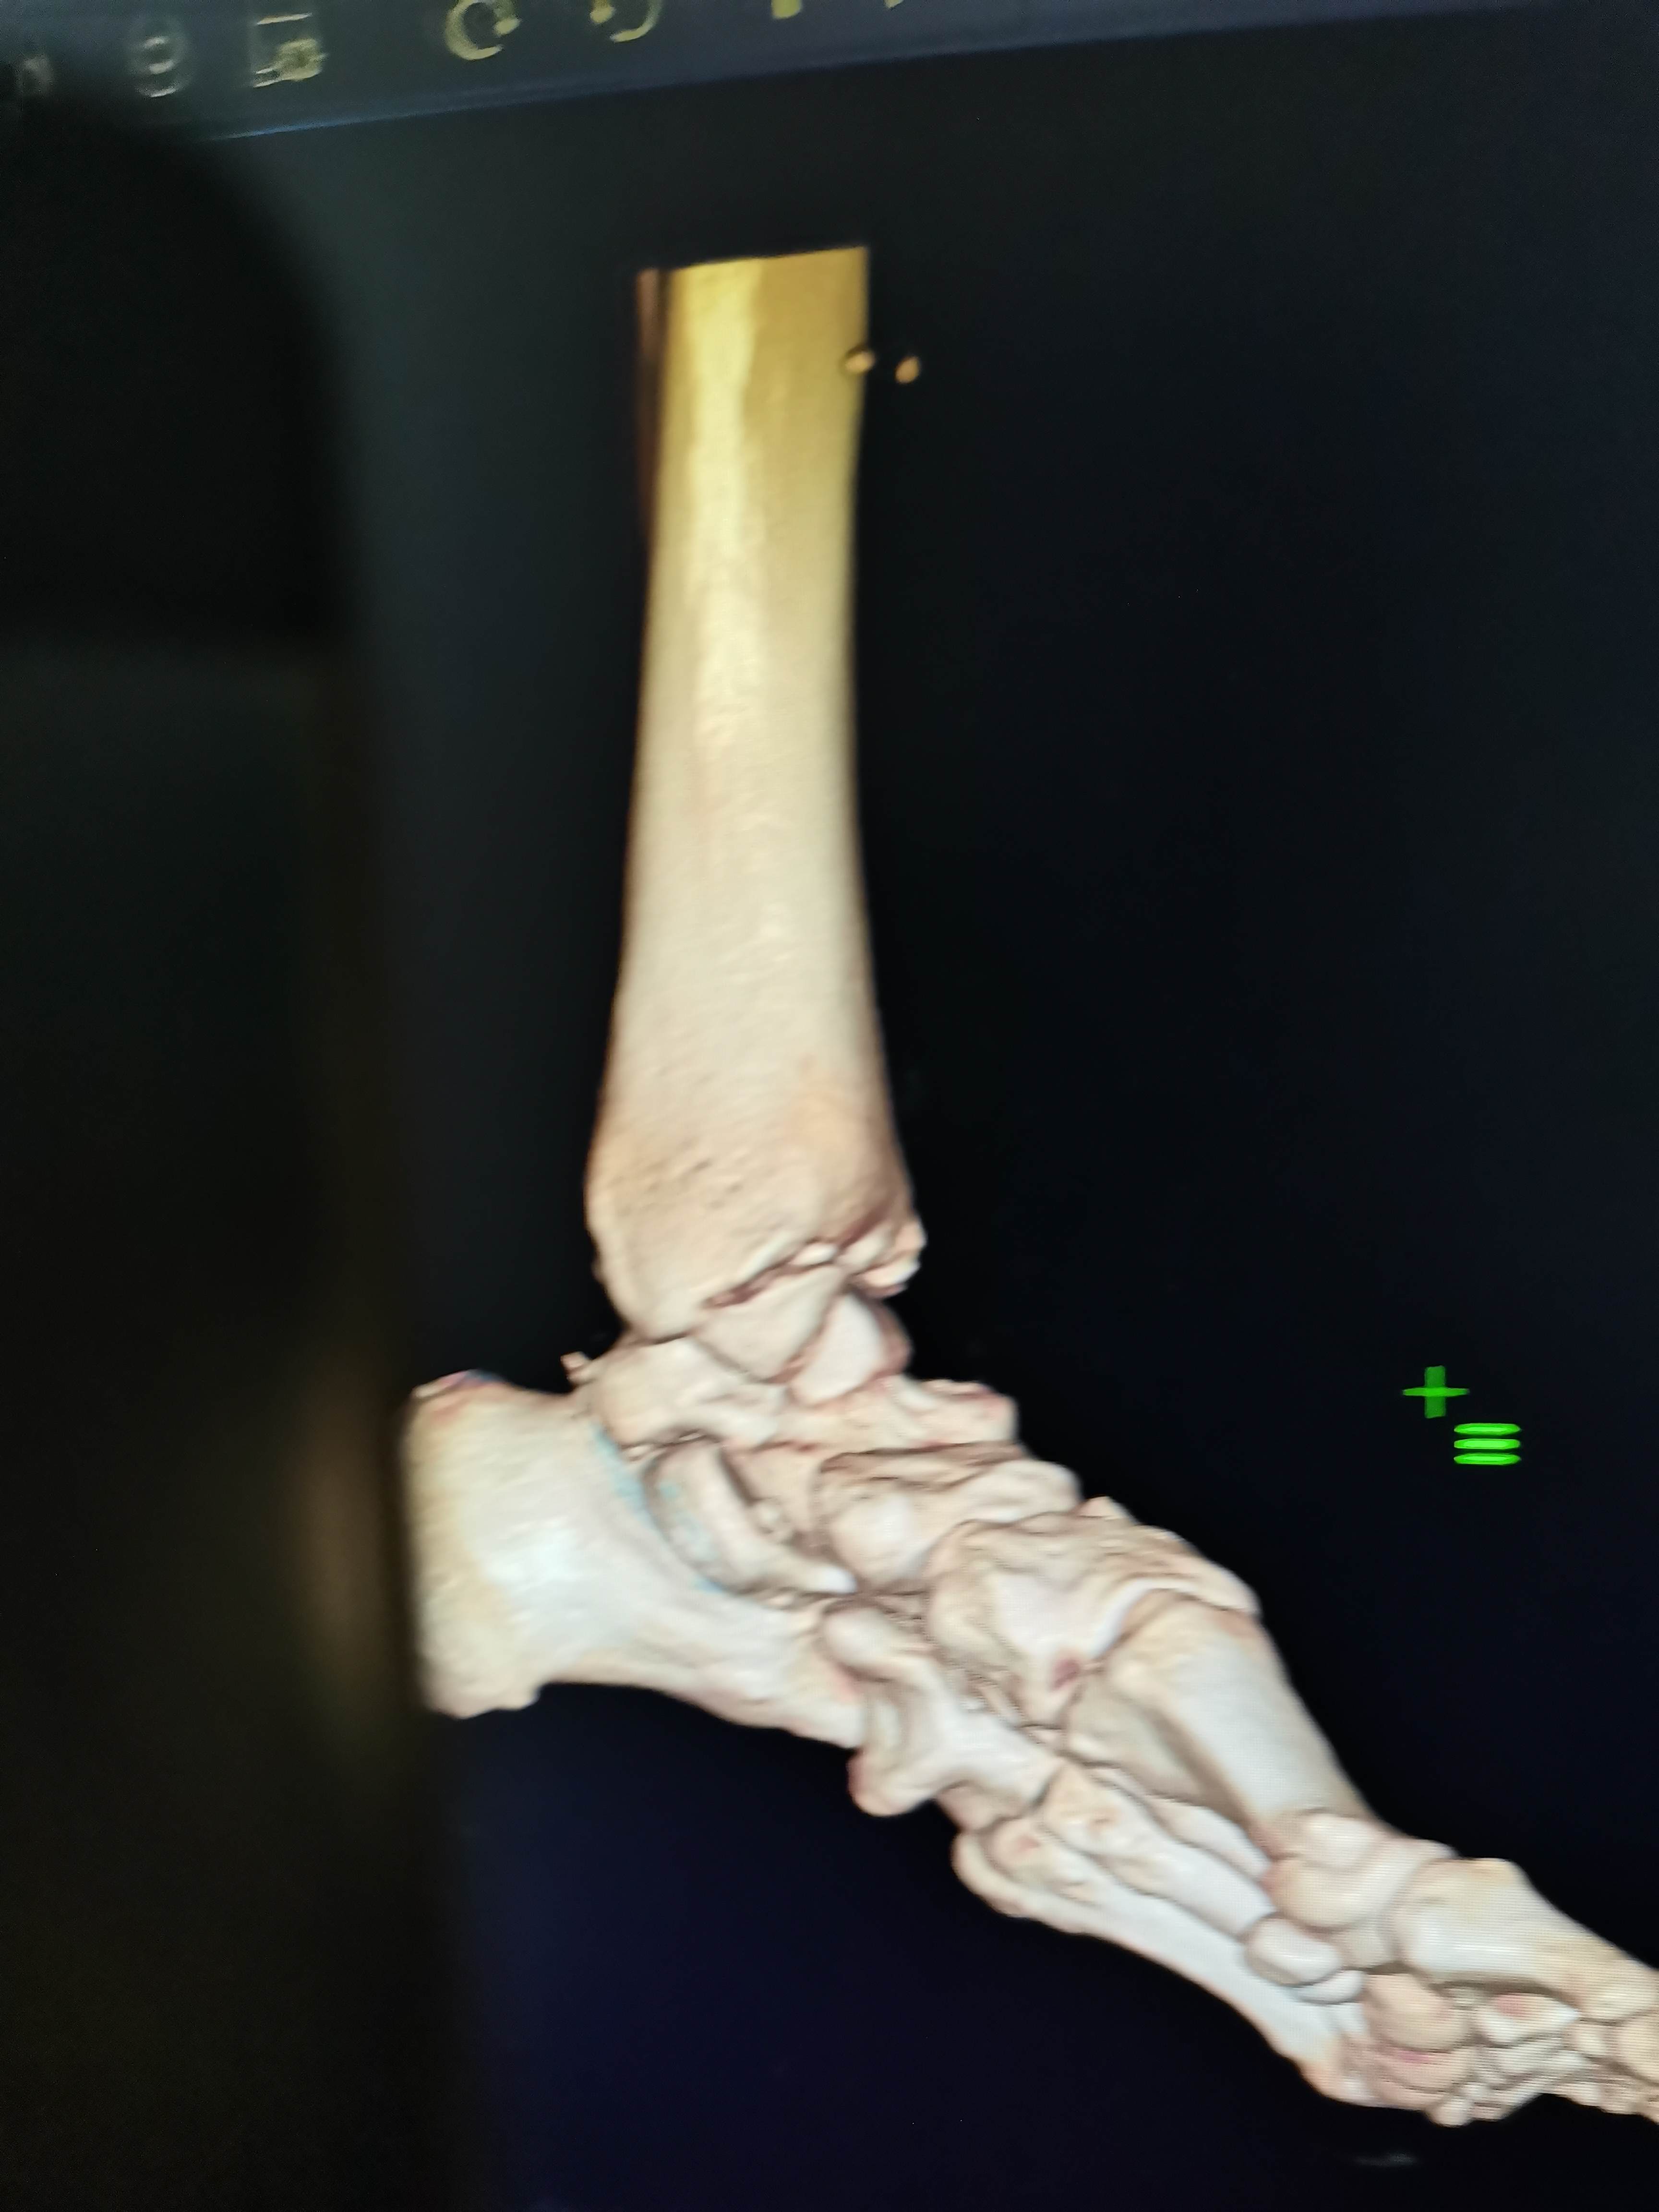

讲明白道理后取得患者信任,入院做了三维CT真像慢慢浮出水面,看到这个您是不是觉得收获很大

三维重建来的更直观,Tillaux骨块的分型和处理选择大家是否铭记在心呢?我想大多数人跟我差不多,回头去复习下吧。收获会很大

沈通氏线中段,tillaux骨块累及到下胫腓